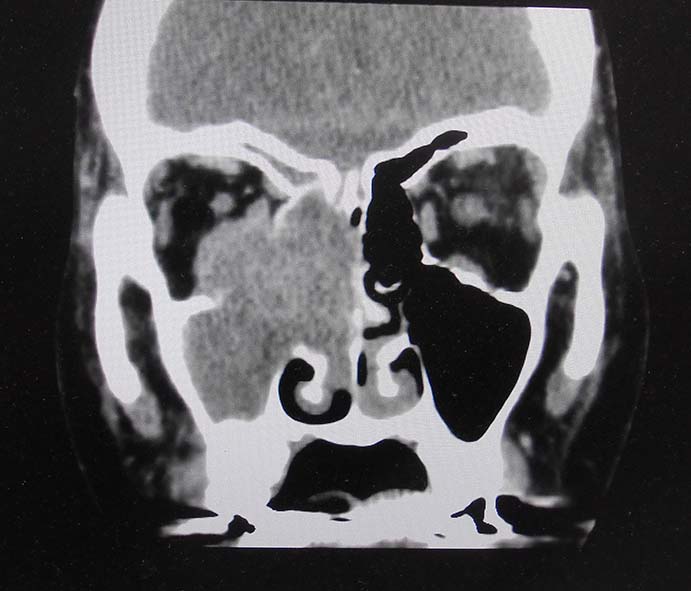

CT所見

副鼻腔腫瘤生検組織

日本病理学会中部支部交見会のスライドより。(S.Suzuki Dr.)